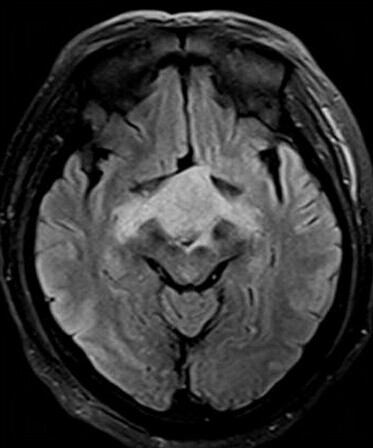

第三脑室脊索样胶质瘤

患者:男,50岁,记忆力下降1月余,双眼视力下降,反应减慢。

【正确答案】D 胶质瘤(第三脑室脊索样胶质瘤)

第三脑室脊索样胶质瘤的特征性表现是:

(1)见于成人,边界清楚,位于第三脑室前部;

(2)T1WI上为低信号,T2WI上呈明显高信号;

(3)增强后明显强化;

(4)肿块累及视交叉及下丘脑,但不浸润周围脑实质。